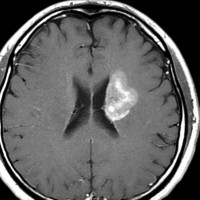

放射線治療13週目

右はガドリニウム増強です。ステロイドとグリセオールの点滴では制御できませんでした。悪性神経膠腫の病名で保険適応があるアバスチン(ベバシズマブ 10mg / kg)の投与を開始しました。